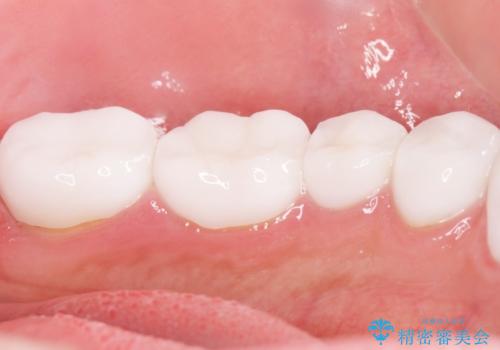

虫歯をしっかりと治療したのち、オールセラミッククラウンによる補綴治療を行いました。

クラウンの種類:オールセラミッククラウン スタンダード

シェード:NW0